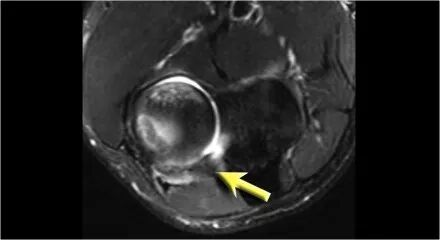

肘关节脱位这是一个患者肘部的侧位片。X光片显示关节积液(红色箭头)和冠状突骨折(黄色箭头)。

下面是MR● 冠状图片:侧副韧带完全剥离(黄色箭头)。桡骨头是半脱位的。由于骨折引起的冠突骨髓水肿(红色箭头)。● 矢状面观:桡骨头稍后有点半脱位(黄色箭头)。大量积液和囊后破裂。● 由于冠状突的撞击(红色箭头)导致的头颅后侧的挫伤。所有这些迹象都是后脱位的结果。